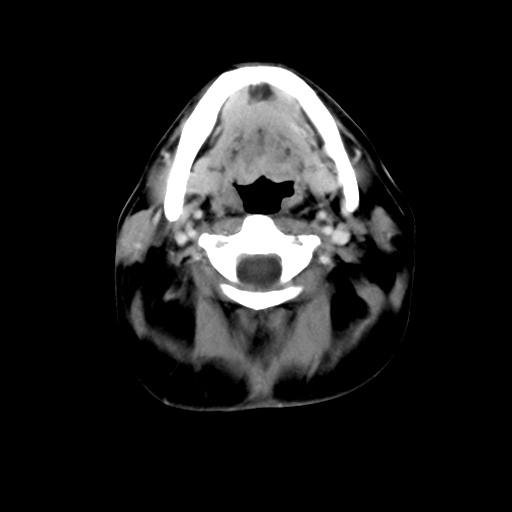

标题: CT24019:男,45岁,发现颈部肿物5个月。 [打印本页]

男,45岁,发现颈部肿物5个月,彩超示:双侧颈部及下颌部软组织增厚。

考虑双侧颈项部良性对称性脂肪增多症。